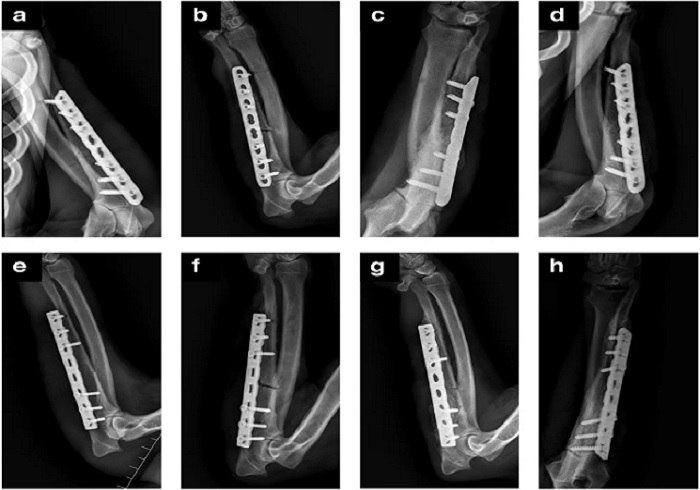

Очень сложные травмы и переломы, которые случаются у военных, требуют огромных усилий и долгого времени для заживления, а новый каркас, который разработан на базе стекла, альгината и наносиликата, очень сильно способен помочь в росте стволовых клеток кости, ускоряя в разы заживление переломов.

Испытывая на крысах такую конструкцию, ученые смогли увеличить время заживления травм на 84% из-за использованию своего нанокаркаса.